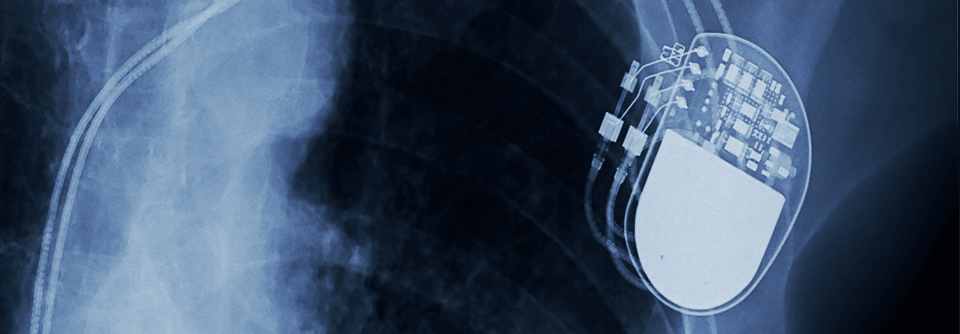

Vor dem Lebensende muss die Schockabgabe eines implantierten Defibrillators inaktiviert werden. Vor dem Lebensende muss die Schockabgabe eines implantierten Defibrillators inaktiviert werden. © iStock/LPETTET